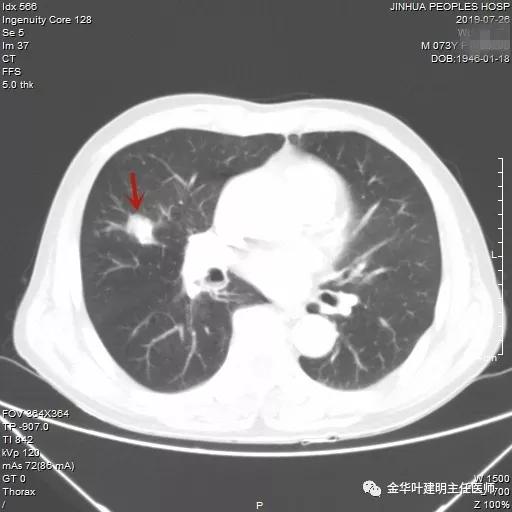

吴某不同意肺穿刺,咳嗽咳痰好转后就出院了。此后于今年6月份回院复查,仍然住在内科,这次想通了,同意肺穿刺,结果病理果然是肺癌,是低分化鳞癌。因为吴某与本院一院级领导是同村的,便让我去会诊。我觉得虽然从病灶来看可以手术,纵隔内也无明显转移的肿大淋巴结,相关检查也无远处转移证据。但患者年纪较大,平时有慢支与肺气肿,发作时还有喘憋症状,肺功能也示重度混合型通气功能障碍,MVV重度下降。询问吴某,平时一口气走上3楼是有困难的,所以行右肺上叶切除术后出现呼吸功能不全的概率还是比较高的,手术存在较大风险。争取手术也是为争取根治以至得到较长期生存的机会。若同意手术,也要家属与患者都十分理解,并对术后需要呼吸机辅助以及无法脱离呼吸机支持都有充分的思想准备。而若放弃手术,则主要是免疫治疗及放化疗,其中放化疗对肺功能也有一定影响,且无法达到根治的目的。我当时告诉吴某儿子,要开,做好术后出现呼吸功能衰竭的准备,且不能责怪我的同事和我本人;若暂不手术,也可回当地考虑保守治疗;当然也可先戒烟、锻炼肺功能、使用支气管扩张剂等改善肺功能,较短时间内再回院复查肺功能,再争取手术。吴某当时办理了出院手续,也没有与我们确认是否考虑手术。下面是当时6月份时候的片子以及肺穿刺情况:

绿色箭头示穿刺针,红色箭头示肿瘤